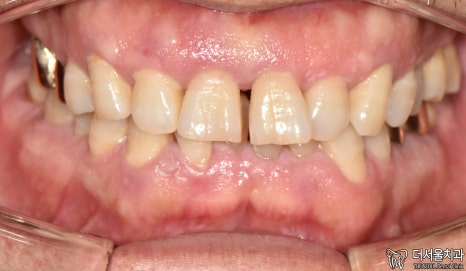

1. 구강 체크

현충일 공휴일 정상진료

서현역 치과를 찾아오셨던 환자분은

앞니와 왼쪽 끝 어금니에

이상 증세를 느껴 찾아오셨습니다.

겉으로 봤을 때는 큰 문제는 없는 것처럼 보입니다.

그럼 대체 무슨 문제가 있는 걸까요?

겉으로 보여지는 것이 아닌,

속을 들여봐야 알 수 잇겠네요.

엑스레이 촬영을 통해 체크해보겠습니다.